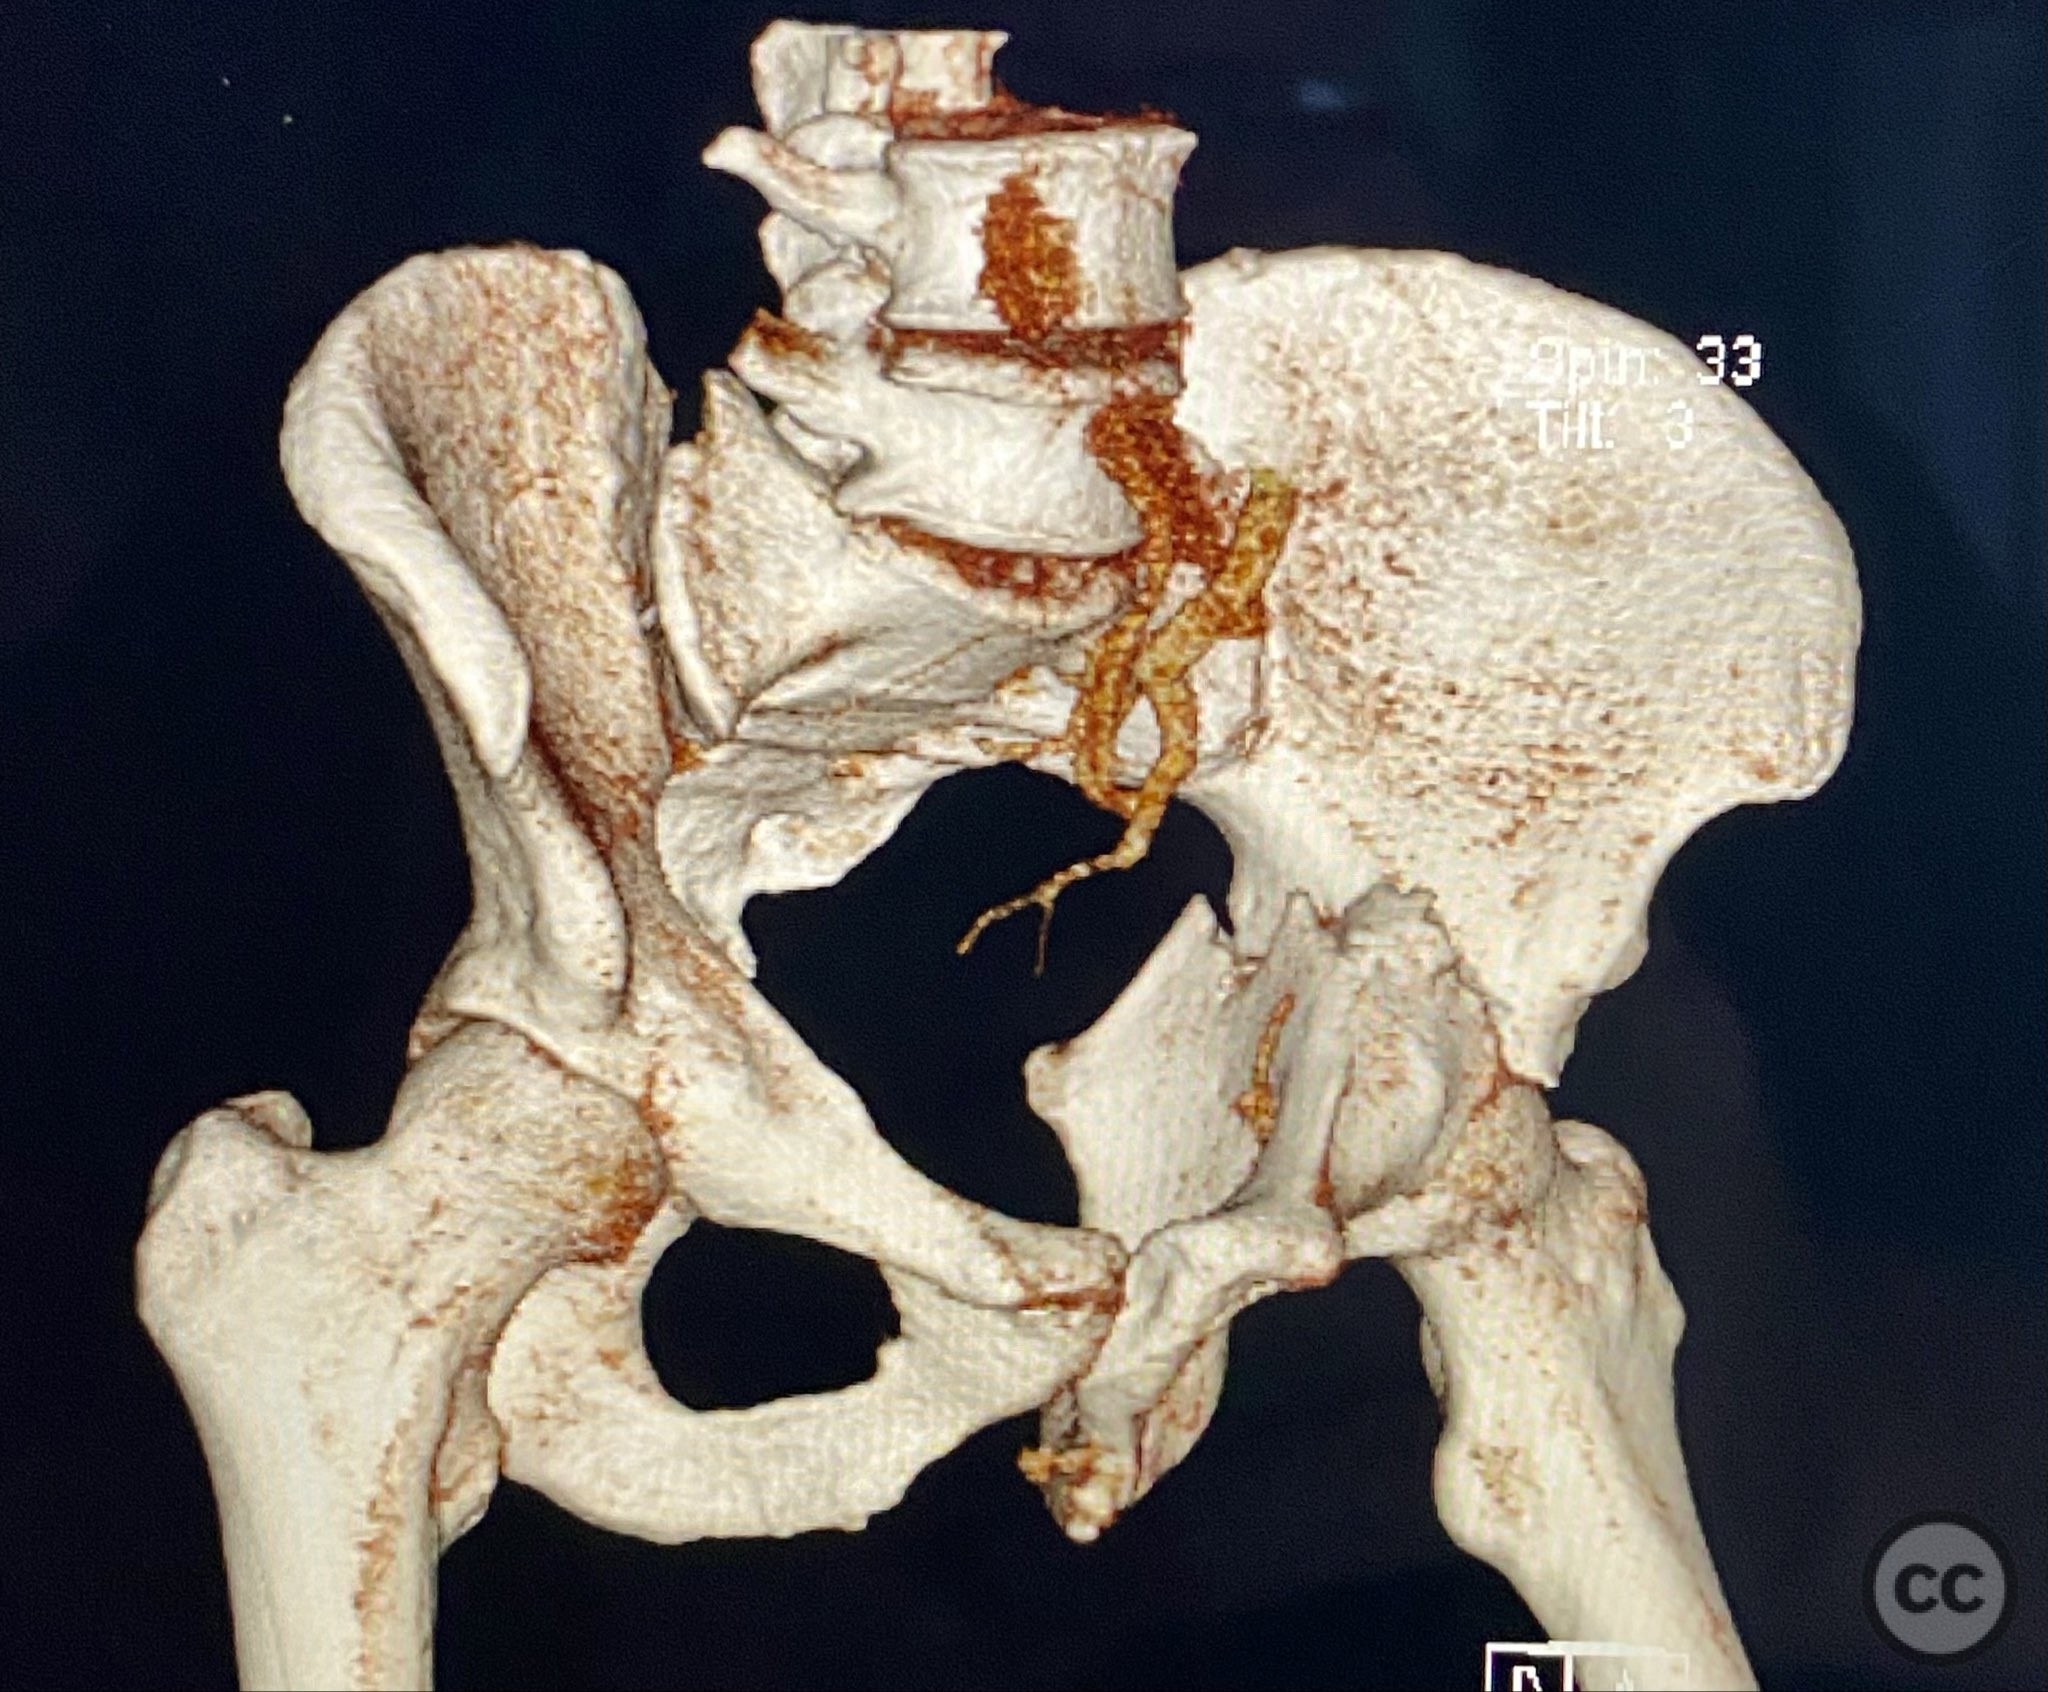

Clinical and radiological findings:  Adult male with a closed, comminuted left femoral shaft fracture and complex pelvic ring injury. Initial imaging demonstrated bilateral sacroiliac (SI) joint disruptions and a left-sided transtectal transverse acetabular fracture (Letournel-Judet: transverse type), with the fracture line exiting through the posterior wall region but without a discrete posterior wall fragment. The femoral head was displaced caudally, following the unstable distal acetabular segment, resulting in loss of congruency with the intact acetabular dome. There was also a symphyseal disruption. No associated abdominal, visceral, thoracic, cranial, or other injuries were present. Application of a circumferential pelvic binder resulted in visible changes in pelvic alignment on imaging. AO/OTA Classification: - Pelvic ring: 61-C1.3 (bilateral SI joint disruption, complete instability) - Acetabulum: 62-B1 (transverse fracture) - Femur: 32-C3 (comminuted diaphyseal fracture)

Planning remarks:  The preoperative plan involved staged management: initial resuscitation and provisional stabilization with a circumferential pelvic binder, followed by operative reduction and fixation of the pelvic ring using an anterior two-pin external fixator for SI joint compression and reduction, percutaneous iliosacral (IS) and transsacral (TS) screw fixation, and subsequent intramedullary nailing of the femur. Definitive acetabular fixation was planned via a posterior Kocher-Langenbeck approach in the prone position.